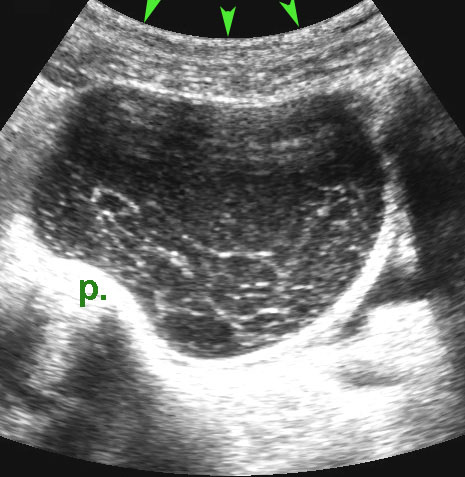

Ca lâm sàng 4

Nang xuất huyết chức năng này là phát hiện tình cờ và có thể dễ dàng ép xẹp vào mỏm nhô (p).

Các bất thường biến mất hoàn toàn trong vòng hai tuần.